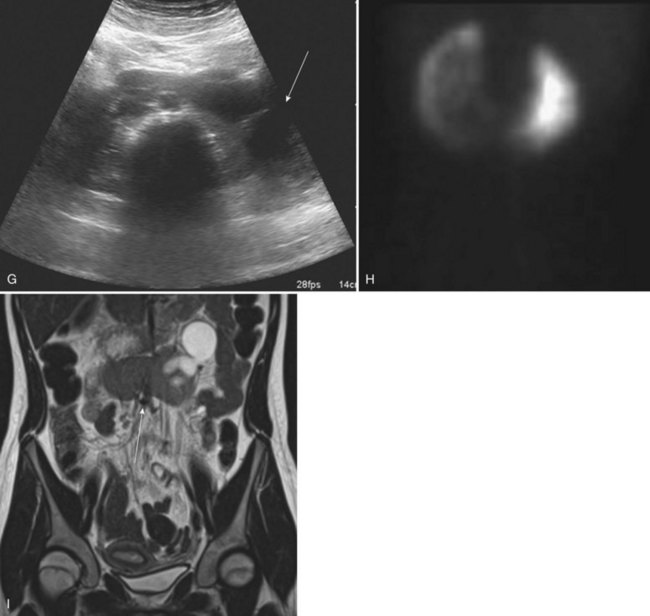

The left side is favored slightly over the right. Pelvic ectopia has been estimated to occur in 1 of 2100 to 3000 autopsies (Stevens, 1937). A solitary ectopic kidney occurs in 1 of 22,000 autopsies (Stevens, 1937; Hawes, 1950; Delson, 1975). By 1973, only 165 cases of a solitary pelvic kidney had been recorded (Downs et al, 1973). Bilateral ectopic kidneys are even more rarely observed and account for only 10% of all patients with renal ectopia (Malek et al, 1971) (Fig. 117–10).

Figure 117–10 One-day-old boy with a right retrovesical pelvic kidney demonstrated on (A) transverse ultrasonogram of right pelvis. B, Sagittal MRI. Vertebral abnormalities and a portion of a lipomyelomeningocele are also observed. C, Longitudinal ultrasonogram of left multicystic dysplastic pelvic kidney. D, Voiding cystourethrogram shows reflux into dilated, tortuous right megaureter. E, Flow study of dimercaptosuccinic acid shows early activity only in the region of the right pelvic kidney and no uptake on the left. F, Postmortem specimen from a different case showing bilateral pelvic ectopia, anterior orientation of renal pelves, and anomalous blood supply from the aortic bifurcation.

(C, Courtesy of Dr. Sara Milla; F, from Weiss MA, Mills SE. Atlas of genitourinary tract disorders. Philadelphia: JB Lippincott; 1988.)

The classification of ectopia is based on the position of the kidney within the retroperitoneum: The pelvic kidney opposite the sacrum and kidneys below the aortic bifurcation are the most common sites of ectopia; the lumbar kidney resides near the sacral promontory in the iliac fossa and anterior to the iliac vessels; and the abdominal kidney is above the iliac crest and adjacent to the second lumbar vertebra (see Fig. 117–10).

With the increasing use of various imaging modalities, the incidence of an asymptomatic ectopic kidney is increasing. Most ectopic kidneys are asymptomatic. Vague abdominal complaints or ureteral colic secondary to an obstructing stone are the most frequent symptoms leading to the diagnosis of an ectopic kidney. The abnormal position of the kidney results in a pattern of direct and referred pain that is atypical for colic and may be misdiagnosed as acute appendicitis or as pelvic inflammatory disease in female patients. Symptoms rarely occur due to adjacent organs to the ectopic kidney. Renal ectopia may also present with a UTI or a palpable abdominal mass. Seven cases of concomitant renal and ureteral ectopia presenting with urinary incontinence have been reported (Borer et al, 1993, 1998). The difficulty in diagnosing this condition is related to the poor function of these ectopic kidneys. The kidneys may be very small and/or dysplastic with essentially no function leading to the misdiagnosis of URA. DMSA scanning or MR urography may both be necessary to diagnose these unusual cases (Borer et al, 1998; Leitha, 1998; Pattaras et al, 1999) (see Fig. 117–10).